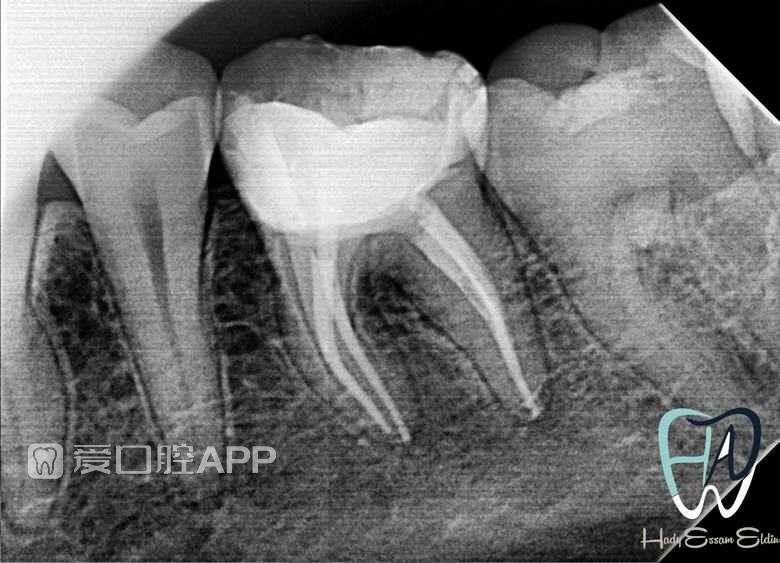

看个根充 —— 下6

by Hady Essam Eldin